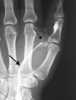

Osteochondritis dissecans (OCD or OD) is a joint disorder primarily of the subchondral bone in which cracks form in the articular cartilage and the underlying subchondral bone. OCD usually causes pain during and after sports. [Source: Wikipedia ]